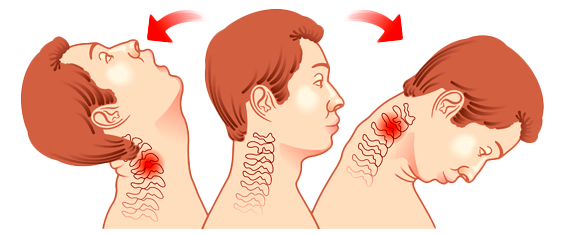

WHAT IS WHIPLASH?

Whiplash, or sometimes called neck strain, refers to an injury of the neck that is the result of a sudden excessive force that causes the neck and head to jerk forward and then backward or vice versa, such as in an auto crash which causes damage to the muscle or tendons (the bands of tissue that connect muscles to bones). Similarly and yet different, neck sprains are caused by tearing of the ligaments (the tissues that connect the bones to each other). Both strains and sprains typically affect muscles, discs, nerves, ligaments, and tendons in the delicate structure of the neck and are treated similarly. These injuries can also occur in contact sports, other activities, or work accidents that might involve a sudden impact.